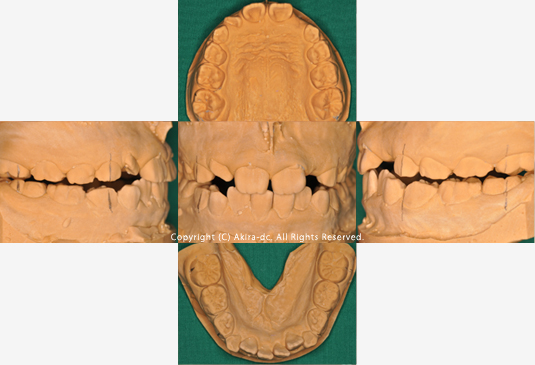

初診時模型写真

このまま放置して様子を見て良いのでしょうか?当医院では悪習癖や顎の発育を考えて早期の段階からのアプローチをお薦めしています。

2年4ヶ月経過 模型写真

歯並びにまだ乱れはあるものの3番目の歯が生えるスペースが確保できてきました。そこで、歯並びを整えるための装置を作るために型採りを行います。

| 術前 正面写真 | 術後 正面写真 |

| 術前 上顎写真 | 術後 上顎写真 |

| 術前 下顎写真 | 術後 下顎写真 |